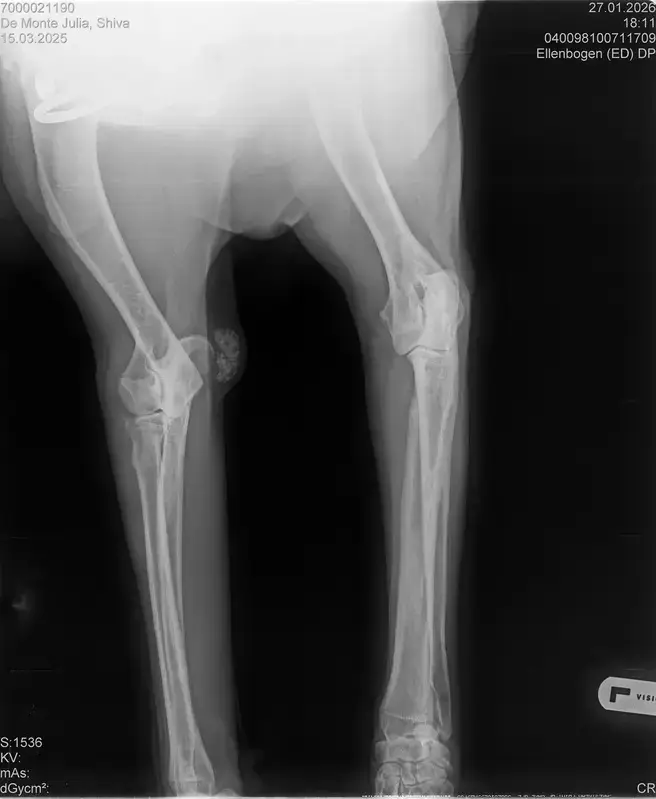

• Naja die Diagnose kommt von einem „Facharzt“, lt TA war ihrerseits alles i.O. Sie wollte noch sicher gehen und die Bilder zur weiteren Befundung einschicken und das kam dabei raus. Und der Therapievorschlag beläuft sich auf Ruhe, Ruhe und noch mehr Ruhe. Und einer Schmertherapie von Gabapentin 800mg 1/2 Tablette 2x tgl, Carprodyl 120mg 1 1/2 Tabletten 1x tgl und TamaCan CBD Tropfen 10-15 Tropfen 2x tgl. 1x in der Woche soll ich telefonisch Auskunft geben wie es Shiva geht. Das ganze mal für 14 Tage. Sie meinte noch sie hat viele Junghunde die ein Leben lang Schmerzmittel nehmem müssten. Die Röhrenknochenentzündung heilt in der Regel von selber der Rest gehört beobachtet… Ich weiß im Moment auch nocht so recht.. Er tut mir nur wahnsinnig leid mit sovielen Diagnosen und für mich war erstmal vorrangig ihn schmerzfrei zu bekommen. Das ist er inzwischen und versteht die Welt nicht mehr warum er nicht wie sonst spielen und arbeiten darf. Im Anhang noch Röntgenbilder falls sich jemand damit auskennt bzw Interesse hat..

• Ok, die Röntgenbilder sind aber auch extrem schlecht.

Panostitis ist idR sehr schmerzhaft, aber nicht unüblich und heilt in der Regel von alleine aus, wichtig dabei ist schonen und Entzündungshemmer zu geben, damit das nicht chronisch wird. Ich denke, dass die Akut bemerkbaren Schmerzen hauptsächlich davon kommen. Also da passt die Empfehlung deiner TÄ für's Erste auf jeden Fall.

Wenn dieser Panostitis-schub rum ist, würde ich dem Rest nochmal nachgehen. Man kann bei Dr. Tellhelm ( SV Gutachter) ein privatgutachten in Auftrag geben, das kostet um die 100€. Da kriegst du halt ne konkrete Einstufung und nicht "verdacht auf" und "könnte hiermit ODER damit in Verbindung stehen", etc.

Ich denke aber, dass du für ein Gutachten von Tellhelm nochmal neu röntgen lassen musst, ich finde, dass das Bild der Hüfte (HD und LÜW wird da beurteilt) und die Draufsicht auf die Ellenbogen (nötig zur Beurteilung von ED) unterirdisch sind!